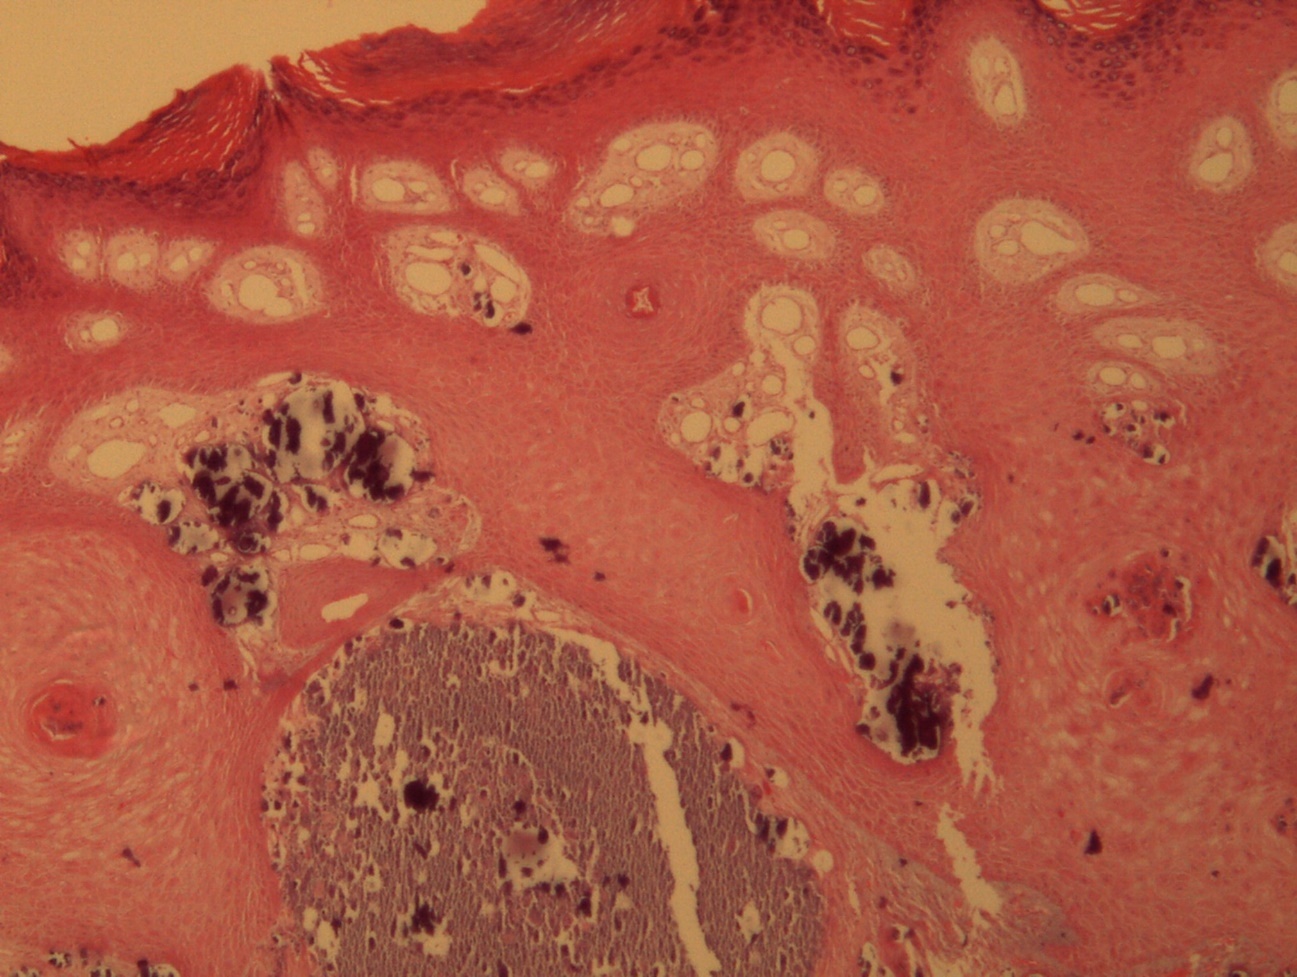

A 9-year-old male patient who was treated in the dermatology service for a progressively growing keratotic nummular dermal lesion on the right knee. With the clinical judgment of viral wart, the lesion was removed. In the Pathology Service, a nummular keratotic lesion of 0.5 cm in maximum dimensions was received, which crackled when cut. Figure 1, Figure 2, Figure 3, Figure 4, Figure 5

Figure 1.Hyperkeratosis, hypergranulosis, proliferation of dermal vessels, and surface and deep calcium deposits. HE. 100x.